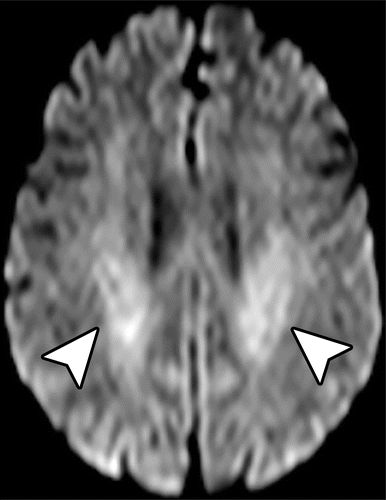

Imagem 4

5-fluorouracil (5-FU) e fludararabine